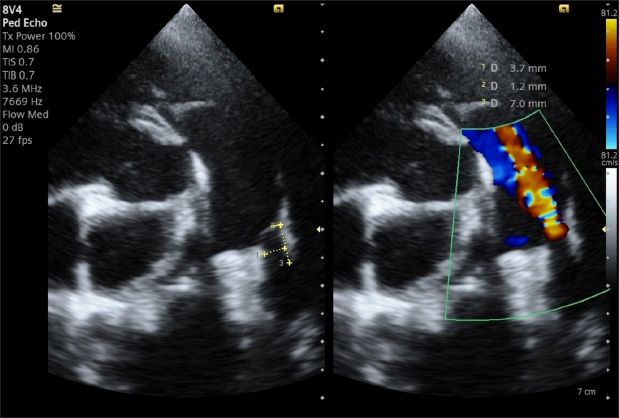

A transthoracic echocardiogram (TTE) (Siemens Acuson Juniper, Probe: 8V4, Siemens Healthcare, Erlangen, Germany) revealed mild left atrial and left ventricular dilation: Left atrium/aorta ratio: 1.8 ( reference value < 1.6), normalized to body weight), left ventricular internal diastolic diameter: 1.98 (reference value: ≤ 1.7), and left ventricle apical four-chamber view end-diastolic volume (Simpson biplane method): 23.6 mL (reference value < 20.1 mL), (Wess et al. 2021). It also revealed a small PDA, with approximate MDD and ampulla diameters of 1.2 mm and 3.7 × 7 mm, respectively, and a length of 7 mm (Fig. 2).

Doppler echocardiography confirmed left-to-right flow across the PDA with pressure gradients of 113.30 mmHg in systole and 59.5 mmHg in diastole.

Fig. 2. Transthoracic echocardiography, cranial left lateral view, optimized for PDA visualization and its measurement (A) and and left-to-right flow on CFM Doppler (Dual-mode).